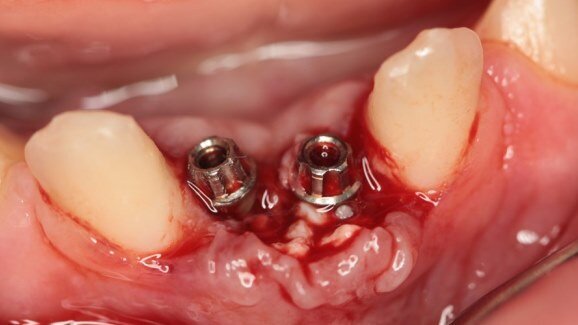

Zdjęcie śródzabiegowe, wszczepienie miniimplantów w pozycji siekaczy centralnych żuchwy, znaczny deficyt tkanki kostnej, augmentacja od strony przedsionka (DDBM).

Po 7 miesiącach zdecydowano o implantacji w odcinku przednim żuchwy. Wykonano badania radiologiczne: pantomogram i CBCT w celu określenia warunków do optymalnej pozycji wszczepów w trudnych warunkach kostnych. Zabieg przeprowadzono w znieczuleniu nasiękowym, nacięto i odwarstwiono płat śluzówkowo-okostnowy i pogrążono implanty miniSky 2,8 mm. Udzielono wskazań pozabiegowych i polecono zgłosić się na zdjęcie szwów 10 dni później. W czasie wizyty kontrolnej stwierdzono prawidłowe gojenie się rany. Po kolejnym tygodniu na dobudowie akrylowej zacementowano (cement kompozytowy Flow Kerr) odbudowę tymczasową, wykonaną z akrylu Protemp.